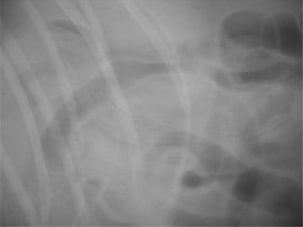

術前レントゲン

腹部臓器が胸腔内に脱出し、腹部と胸部の境界および心臓や肺の陰影が不明瞭になっています。また、胸腔内に消化管のガス陰影が認められます。

術後レントゲン

腹部臓器が腹腔内に戻り、腹部と胸部の境界および心臓や肺の陰影が明瞭に見えるようになりました。